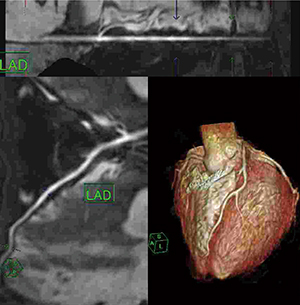

冠動脈の解析結果

心臓MRIの解析結果。冠動脈が明瞭にとらえられている。

3枝だけでなく分岐する血管も可能な範囲で抽出している。

検査では,直前にニトログリセリンを舌下投与する。血管が拡張し,呼吸状態も安定しているうちに,Balanced SARGEシーケンスで冠動脈の撮像を行う。続いてシネMRIを3方向,最後にblack-blood法によるT2強調画像を撮像する。検査時間は30〜40分ほどで,再撮像も考慮して検査枠は1時間を設定する。解析にはワークステーションを用い,マニュアル操作で冠動脈の抽出を行う。

「現状で80〜85%の成功率となっており,十分に心臓に対応できます。ただ,BMIが高いとうまくいかないこともあり,脂肪が軟らかく動きやすいことで心臓の動きが複雑になることが理由として考えられます。今後,横隔膜ナビが三次元的に追従できるようになればアドバンテージがありますし,より簡単に撮像できるようになれば,ECHELON OVALによる心臓MRIは普及すると思います」